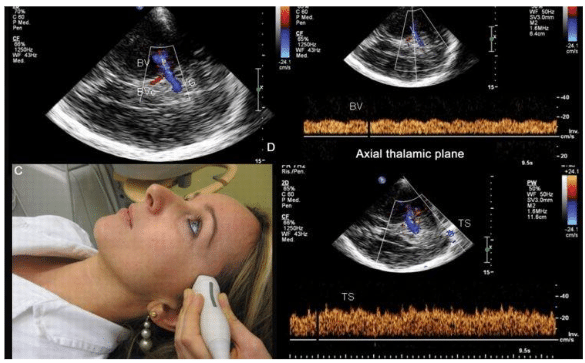

2-Quais exames neurológicos são realizados na Gileade?

Resposta:

São realizados exames como eletroencefalograma de rotina, eletroencefalograma , potencial evocado P300, potencial evocado auditivo, potencial evocado Visual e doppler transcraniano.